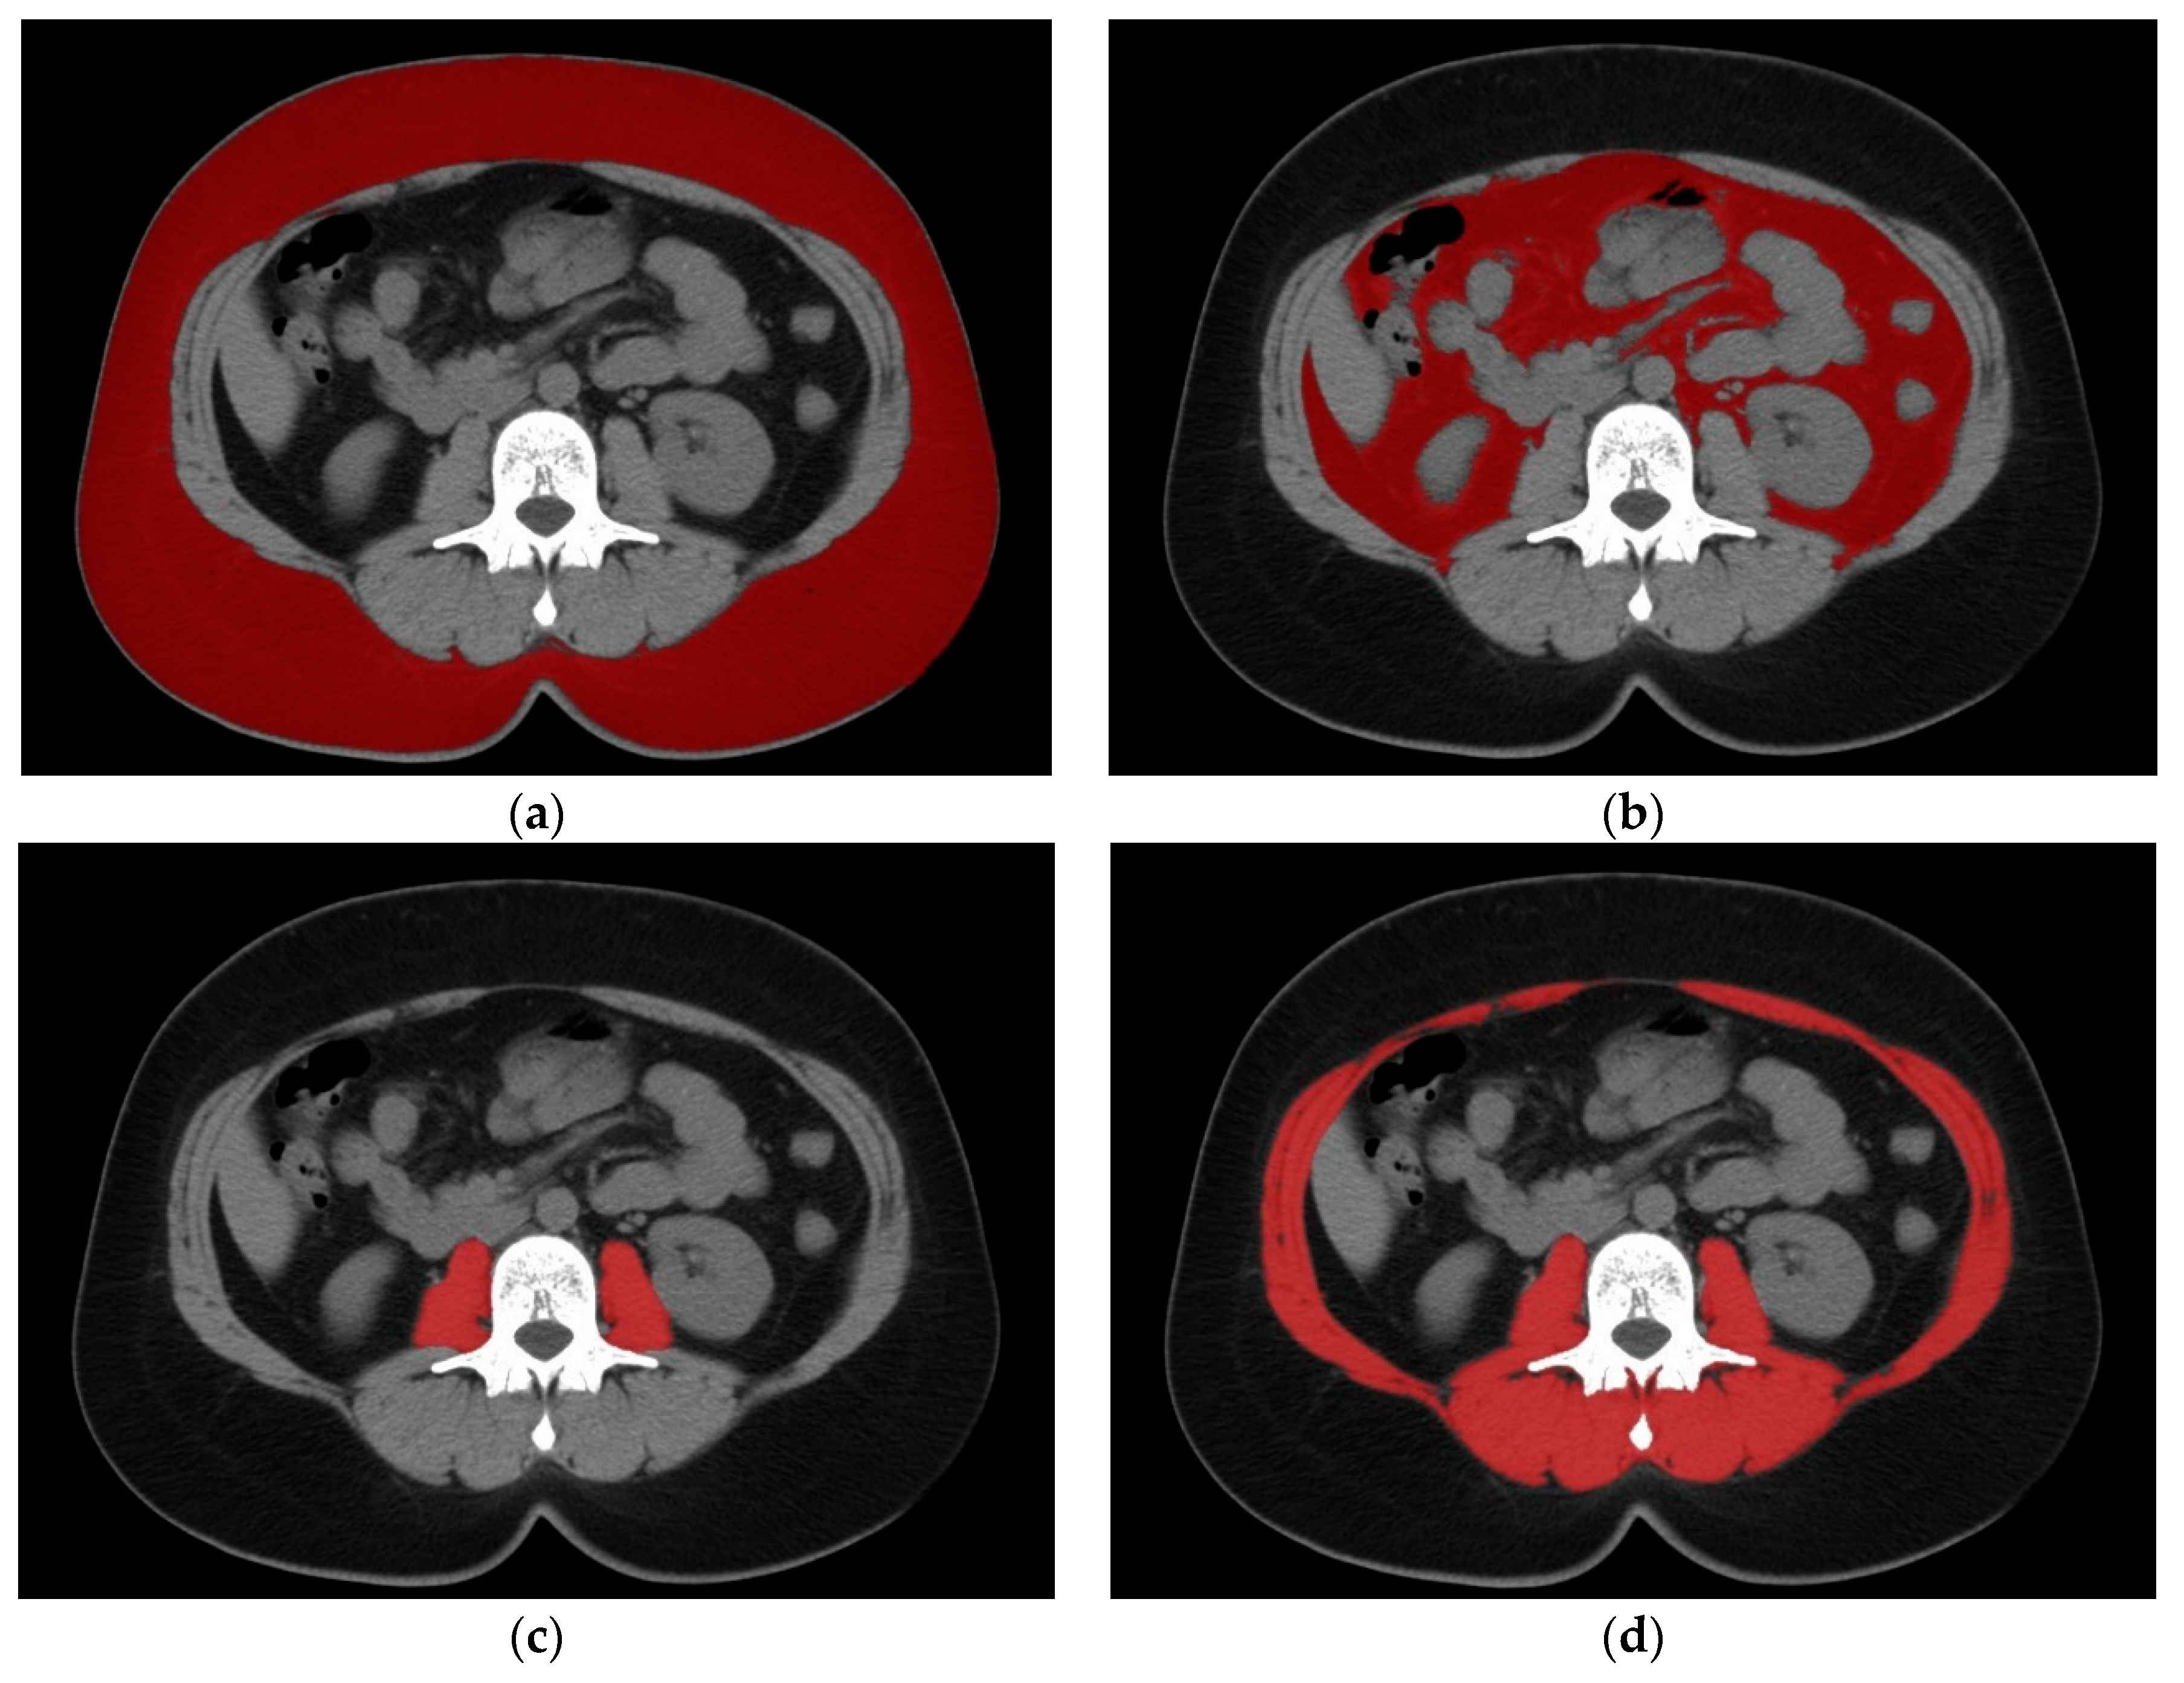

2. Materials and Methods